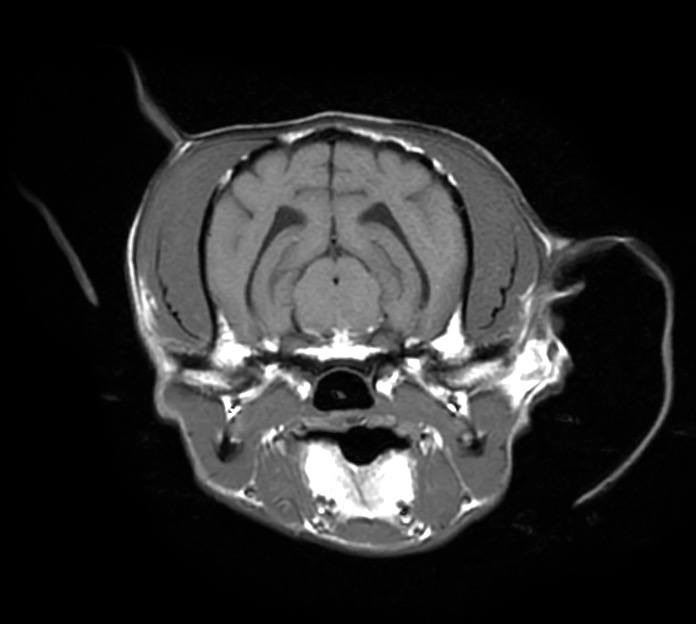

肉芽腫性髄膜脳脊髄炎と診断した犬の1例(MRI、GME、脳炎、神経症状、ふらつく、眼振)

治療開始2週間後に実施した頭部MRI再検査では、脳の浮腫といった脳圧亢進所見、大脳後頭葉領域の炎症所見がすべて改善し、 わんちゃん自身もふらつきや眼振は無くなり、元気や食欲といった一般状態も極めて良好でした。

脳炎は治療をストップすると再発する恐れがあるため現在も治療継続中ではありますが、

早期診断→早期治療を行えたため、現在も良好な経過をたどっています。